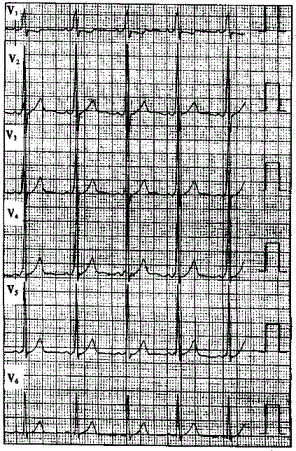

问题 患者男性,40岁,多次发作心悸,心电图一-见下图,显示为预激图形。 ? ? 食管电生理检查诱发了逆向型房室折返性心动过速,该心动过速的折返途径为

选项 A.心房→房室结→心室→旁路→心房 B.心房→旁路→心室→房室结→心房 C.心室→房室结→心房→旁路→心室 D.心室→旁路→心房→房室结→心室 E.以上都不是

答案 B

解析 :食管心房调搏可以诱发心动过速并确定心动过速的发生机制该心电图显示V导联delta波向上,旁路位于左侧;Ⅱ、Ⅲ、aVF导联delta波向上,提示旁路位于左侧壁;当旁路前传有效不应期<270ms或预激综合征合并心房颤动时最短RR间距≤240ms时,提示为高危旁路;逆向型房室折返性心动过速的折返途径为:心房→旁路→心室→房室结→心房